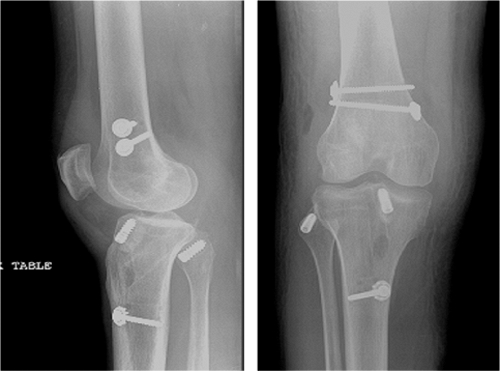

(Figs. 25.12,25.13,25.14).

![]() |

|

Figure 25.12. Postoperative radiographs of ACL/PCL/LCL reconstruction with PLC primary repair.

Figure 25.13. Postoperative radiographs of ACL/PCL/MCL reconstruction.